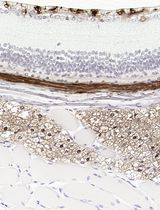

Improved Immunohistochemistry of Mouse Eye Sections Using Davidson's Fixative and Melanin Bleaching

Anne Nathalie Longakit [...] Catherine D. Van Raamsdonk

Nov 20, 2025 1474 Views